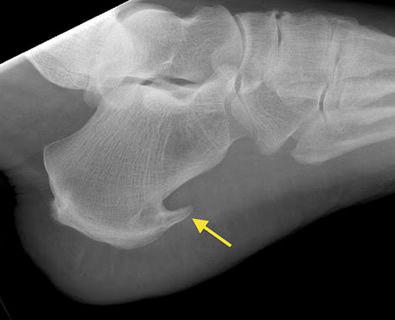

O esporão de calcâneo é uma saliência calcificada que se forma na parte inferior do osso calcâneo (osso do calcanhar). Esta saliência patológica se forma na planta do pé, junto à fáscia plantar, que é um forte tecido fibroso que ajuda a formar o arco longitudinal do pé.

O esporão de calcâneo é habitualmente confirmado, após exame clínico, por exame de raios X. É uma forma de exostose, uma excrescência óssea.

O esporão inferior no calcâneo está localizado na planta do pé e é tipicamente uma resposta à inflamação, à uma fasciíte insercional plantar, ao longo do tempo. O esporão não é uma deformidade aguda. Ele é a resposta à uma irritação/solicitação anômala crônica.